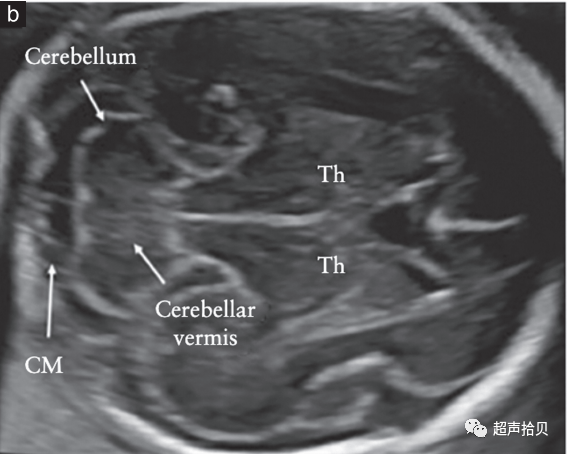

图2胎儿头部的横切面,显示标准的经脑室(a)、经小脑(b)和经丘脑(c)扫描平面。经脑室和经丘脑平面允许评估大脑半球区域的解剖完整性。经小脑平面允许评估后颅窝的小脑和大池(CM)。CP-脉络膜丛、CSP-透明隔腔、TH-丘脑。

大脑

用于胎儿大脑基本检查的标准扫描平面在更新的 ISUOG 指南20中有描述。两个横断面,通常称为经脑室平面和经丘脑平面,可以显示与大脑解剖完整性相关的大脑结构(图 2)。成像伪影掩盖了近端半球(更靠近探头的半球)。应添加第三个横断面-经小脑平面来评估后颅窝。应评估以下大脑结构: